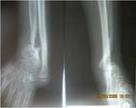

儿童陈旧性孟氏骨折

术前前臂侧位片

术后肘关节侧位片

术后1个月肘关节侧位片

儿童陈旧性孟氏骨折,术前桡骨小头陈旧性脱位,经截骨矫形治疗后1个月,桡骨小头已复位,患儿肘关节屈伸功能(1-2图),前臂旋转功能(3-4图)正常